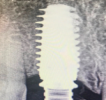

The single tooth implant restoration consists of three parts. Namely, the implant post which replaces the tooth root, the abutment which will support the crown and the prosthetic crown itself. The crown is either cemented onto the abutment or held in place with a screw. The parts of the single tooth implant are bio-compatible to the tissues of the mouth. Therefore, they do not cause any side effects in the oral cavity.

The call to do the implant + crown simultaneously* depends on host of factors including bone density.

We prefer to do the Implants in 1st visit along with temporaries, which should be changed to permanent Porcelain teeth after 6 months time, hence we recommend a second visit to us after at least 6 months. But if the conditions are fine, we can do IMMEDIATE LOADING with Crowns during the same visit. Each visit should be for at least 7-14 days time.